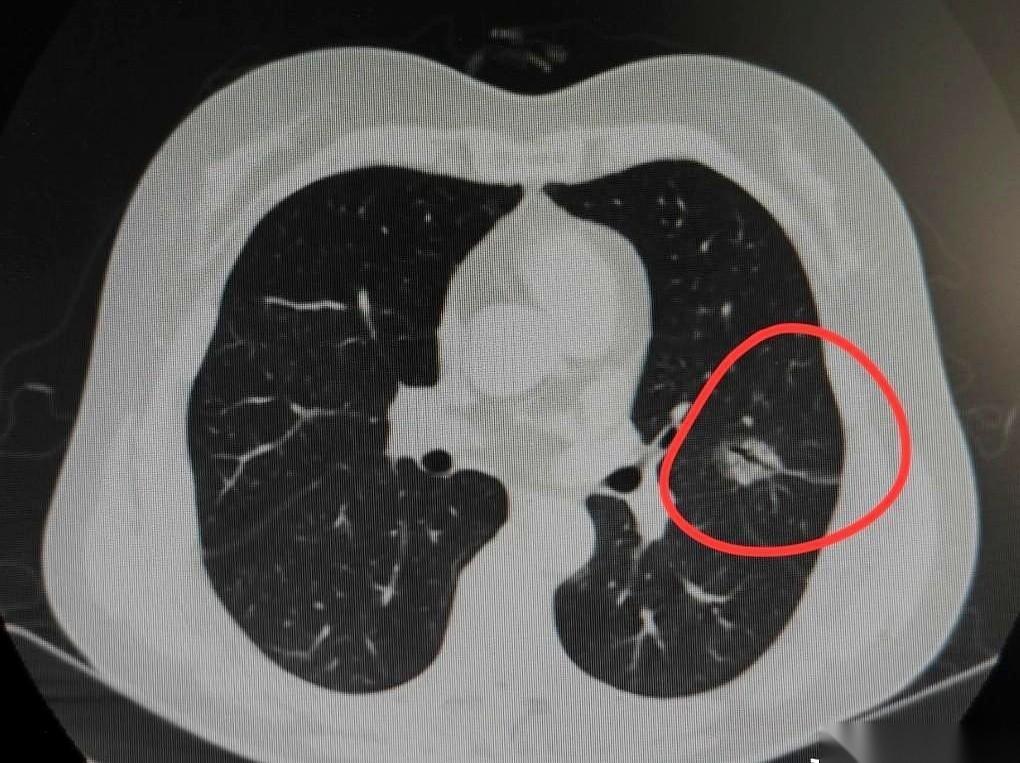

一张CT片子,啪地一下挂在灯箱上。 天津,一个65岁的老太太,本来是看别的病住院,顺手查了一下胸部。结果,就是这张片子,让整个诊室的空气都停了。 一个医生朋友后来跟我讲起这个事,说他当时指尖就点在那个影子上——一个2厘米的毛玻璃块,边缘不清,还死死拽着旁边的胸膜。 家属凑过来,声音都是抖的:“大夫,我们查了,这种是不是叫‘微浸润’?是不是……没那么厉害?” 屋里静得能听见打印机工作的嗡嗡声。 医生没立刻回答,只是把片子放大,再放大,那个影子的轮廓像一朵炸开的烟花,带着毛刺,他用笔尖在片子上轻轻画了一个圈,然后抬头看着家属,一字一句地说:“2厘米,已经没有侥幸的可能了。” “侥幸”两个字,像两根针,扎破了家属脸上最后一点强撑的镇定。 手术同意书签得很快。 几天后,病理报告出来了,几行打印的黑字,结论是:浸润性肺腺癌。 其实从看到片子那一刻,结局就已经写好了。所谓“微浸润”,那都是给1厘米以下、干干净净的小影子留的安慰奖。 体检报告上的一个小点,落到一个家庭头上,就是一场惊天动地的雷。